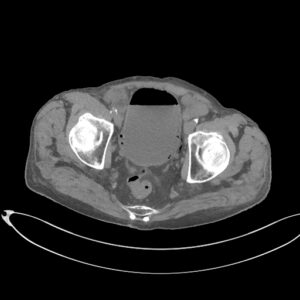

CAZ nr 131: Cistită emfizematoasă

Figurile 1 şi 2: axial examinare CT abdomen şi pelvis fără substanță de contrast

Discuţie caz nr 131: pacient de 85 de ani cunoscut diabetic este adus la camera de gardă pentru dureri abdominale difuze, efectueaza CT fără substanță de contrast deoarece eGFR este 21 mL/min/1.73 m². Se evidențiază pericardita în cantitate medie, mai multe chiste renale – unul spontan hiperdens, multiple plăci aterotrombotice calcificate la nivelul aortei și ramurilor precum și multiple bule aerice în peretele vezicii urinare și conținut hidro-aeric al vezicii urinare. Ultimele două elemente sugerează diagnosticul de cistita emfizematoasă.

DE LUAT ACASĂ!!! Cistita emfizematoasă este o infecție gravă, dar rară, a vezicii urinare, în care bacteriile producătoare de gaze creează bule de aer în peretele vezicii urinare, adesea asociate cu diabetul necontrolat, mai rar cu utilizarea cateterului sau vezica urinară neurogenă. Simptomele includ dureri abdominale inferioare, febră și urinare dureroasă sau frecventă, dar diagnosticul necesită tomografie computerizată pentru a observa gazele. Tratamentul implică antibiotice și gestionarea afecțiunilor subiacente, fiind posibil necesară intervenția chirurgicală în cazurile severe, deși tratamentul prompt duce de obicei la un rezultat favorabil.